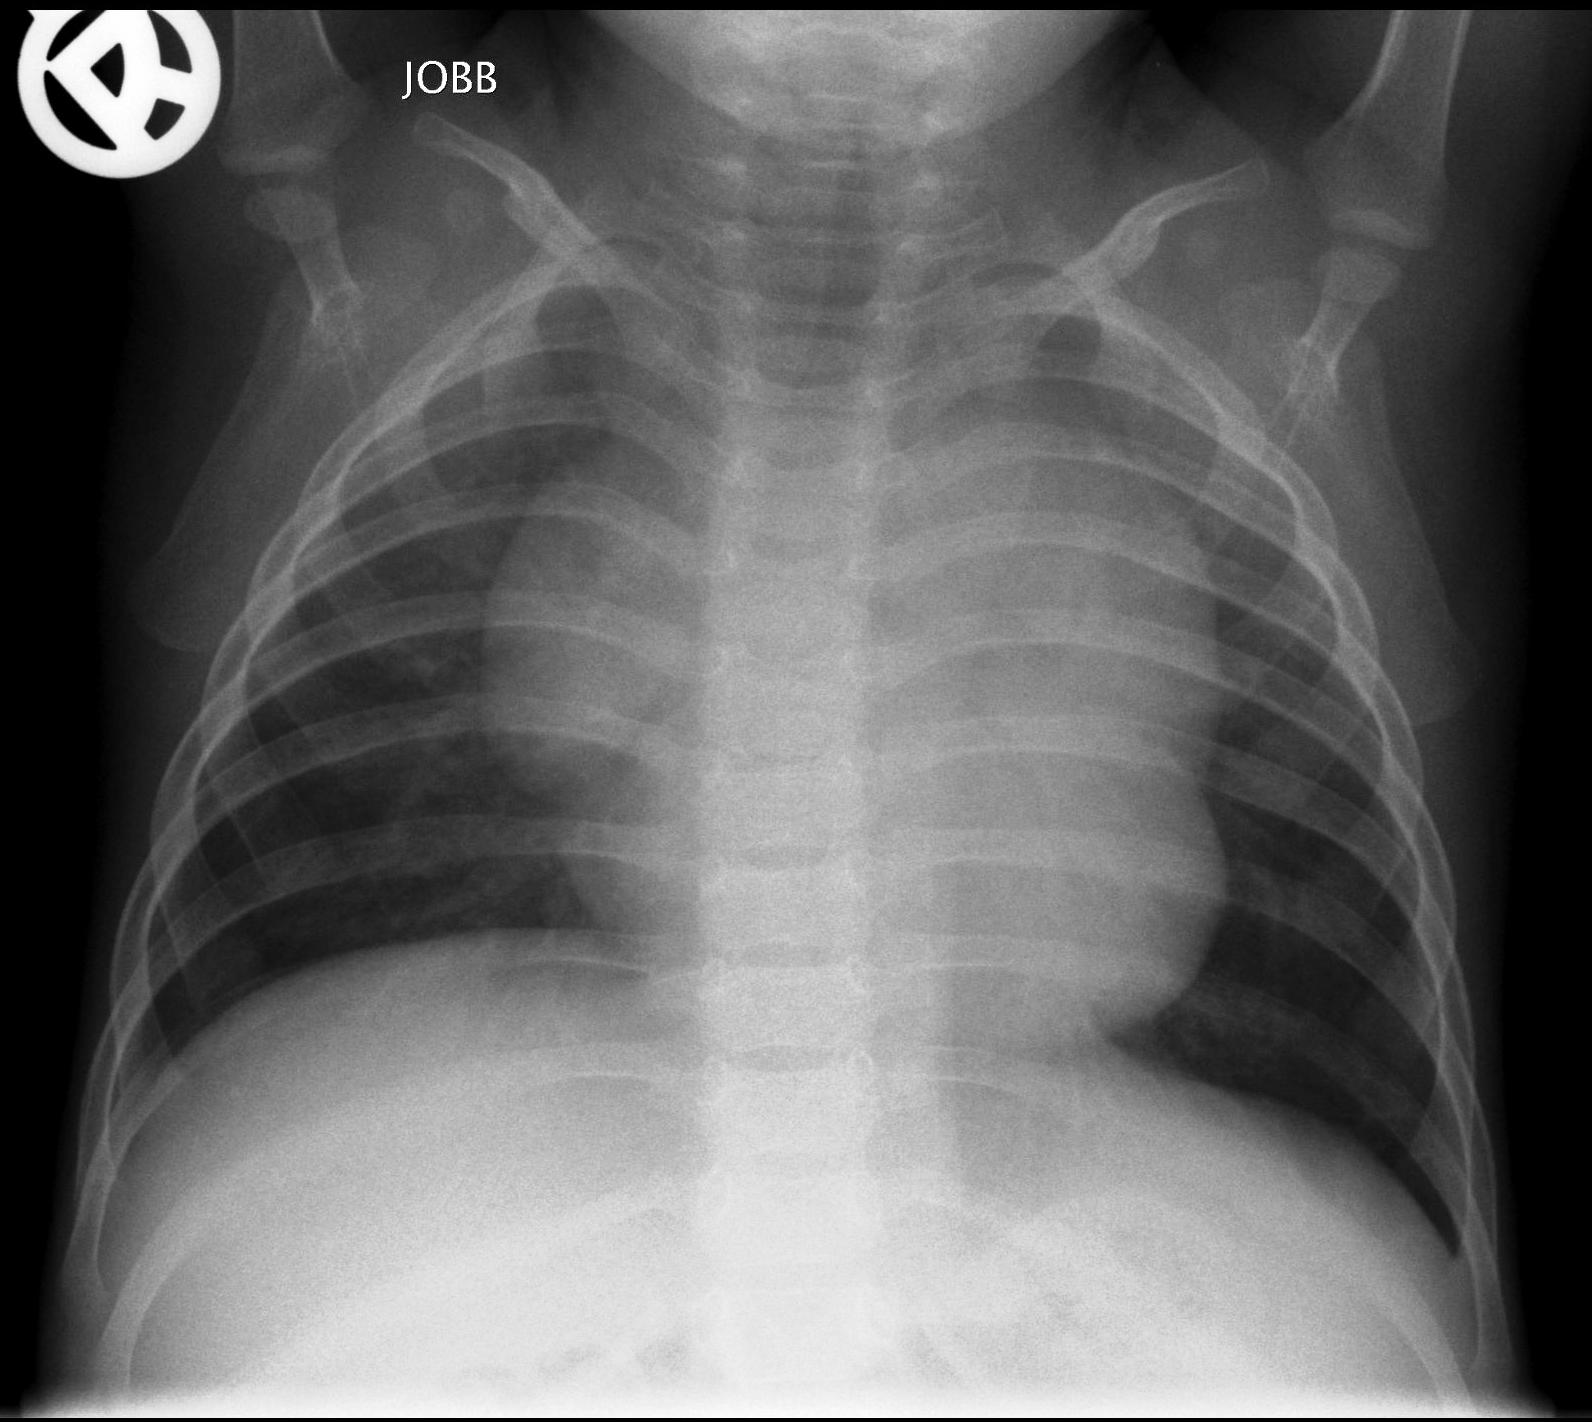

Normal newborn lungs: a newborn’s chest goes through some fundamental changes during the first days of extra-uterine life. The heart is relatively rounded, characterized by the dominance of the right side. The cardio-thoracic index taken in a mid-inspiratory state is between 0.55-0.62. Expiratory state can lead to diagnostic mistakes.

Thymus: is usually made up of two asymmetrical lobes, situated in the anterior-superior mediastinum and shows a great variability of both size and shape. It does not cause any compression on the neighboring organs. On ultrasound examination it appears as a homogenous solid tissue, relatively more hypo-echoic than the thyroid gland. The diaphragm is a bit more elevated in mid-inspiratory state its arch is between the 8-9th rib on the back and at the 6th rib in the front.

Bony thorax: the ribs are horizontal and the sagittal and horizontal diameters of the chest are very close to each other.

1.b. Inspiratory state, the lung is transparent, the heart is normal sized. Ribs run horizontally in infants.